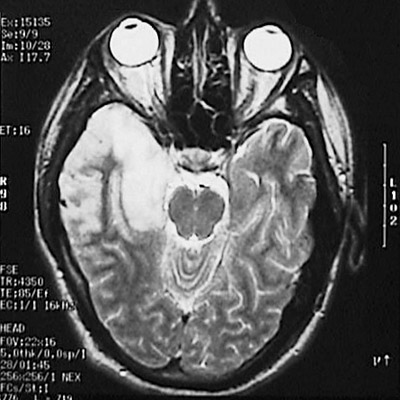

This T2 weighted cerebral MRI scan in axial view demonstrates markedly abnormal signal hyperintensity mainly in the right temporal lobe. This patient had a herpes simplex virus encephalitis.